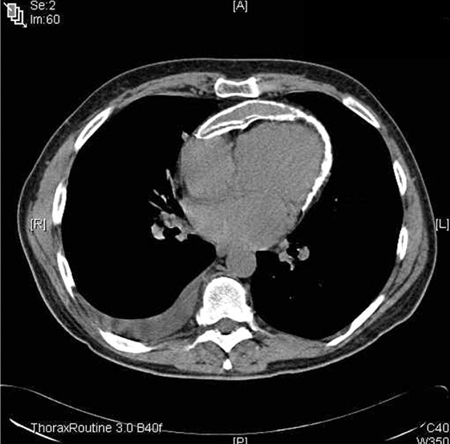

tomografia computadorizada (TC) do tórax ou ressonância nuclear magnética (RNM) cardíaca

Exame

Considere a tomografia computadorizada de tórax ou a ressonância magnética cardíaca, especialmente se a apresentação clínica sugerir pericardite complicada ou se a apresentação for atípica.[1][18][52][53]

O principal achado na pericardite aguda é o espessamento pericárdico.[18] O realce pericárdico pode ser observado na ressonância magnética cardíaca com realce tardio com gadolínio.[54]

A tomografia computadorizada/ressonância magnética também pode detectar complicações como derrame pericárdico ou pericardite constritiva, especialmente quando os achados ecocardiográficos são inconclusivos.[1] A ressonância magnética é mais sensível à pericardite constritiva.[18]

Informações diagnósticas adicionais também podem ser obtidas quando há trauma torácico associado, particularmente quando penetrante; ou no contexto de infarto agudo do miocárdio, carcinoma, infecção pulmonar ou torácica ou pancreatite. Em casos de suspeita de pericardite constritiva, a TC e a RNM oferecem medidas precisas de espessura pericárdica e extensão do espessamento pericárdico, que podem ser úteis para o planejamento pré-operatório antes da pericardiectomia.

[Figure caption and citation for the preceding image starts]: Tomografia computadorizada (TC) do tórax em um bebê com pericardite purulenta, mostrando uma coleção pericárdica com compressão dos ventrículos esquerdo (VE) e direito (VD)Karuppaswamy V, Shauq A, Alphonso N. BMJ Case Reports 2009; doi:10.1136/bcr.2007.136564 [Citation ends].

Resultado

derrame pericárdico ou pericardite constritiva (os achados incluem aumento da espessura pericárdica, calcificação, desvio anormal do septo respiratório ou ressalto septal), dilatação da veia cava inferior e derrames pleurais